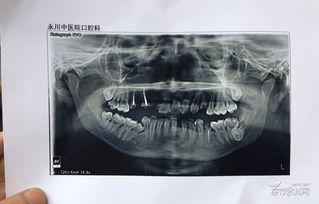

2. 拍片检查:医生会为你拍摄口腔X光片,了解牙齿和骨骼的情况。